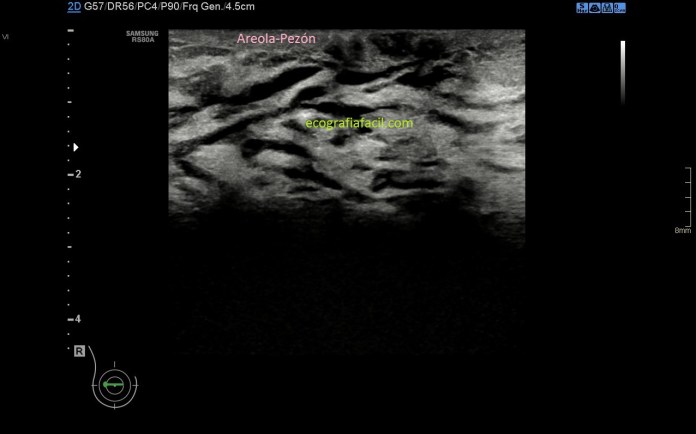

En la imagen 1 vas a ver una anatomía donde la región retroareolar no muestra hallazgos significativos, es decir, no hay conductos visibles. Sería la normalidad.